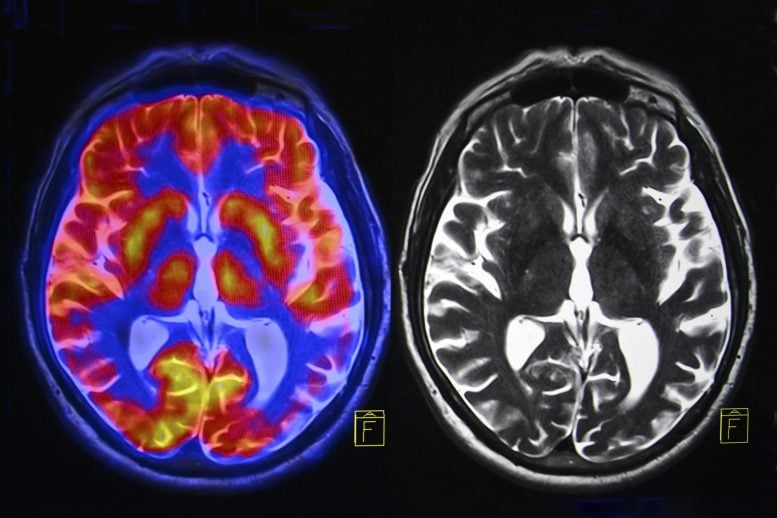

New research suggests menopause is associated with brain volume loss in key regions tied to memory and emotions, along with higher rates of anxiety, depression, and sleep issues. Hormone therapy didn’t prevent these changes, though it may slow age-related declines in reaction speed. Menopause Linked to Brain Changes and Mental Health Challenges New research from […]Health,Brain,Menopause,Psychology,University of Cambridge#Brain #Scans #Reveal #Hidden #Menopause1769473936